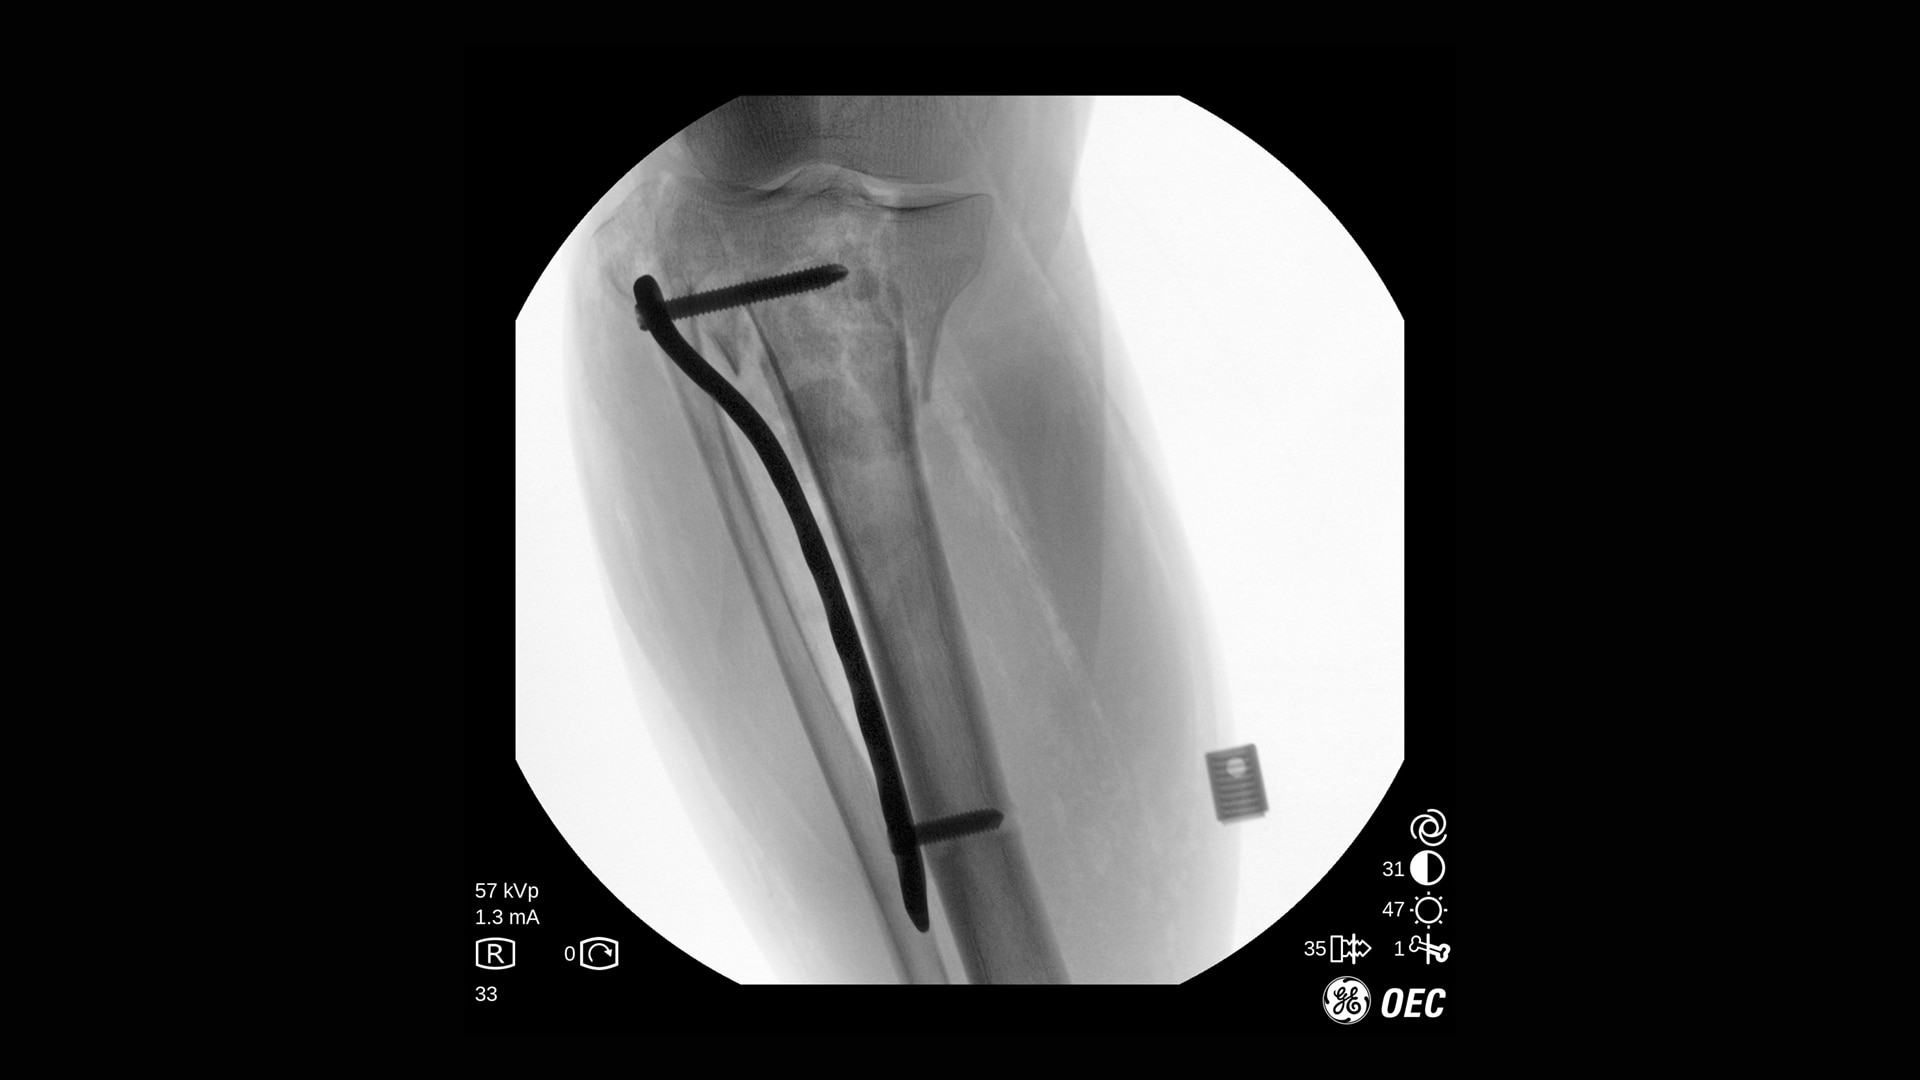

Der OEC One CFD unterstützt ein breites Spektrum klinischer Anwendungen: von endoskopischen Interventionen und Schmerztherapie bis hin zu komplexen Wirbelsäulen- und orthopädischen Verfahren.

Die Bildqualität ist bei verschiedenen Verfahren und Verfahrenseinstellungen essenziell, besonders auf engem Raum. Mit OEC One CFD erleben Sie die Bildqualität, die sie von den OEC mobilen C-Bögen erwarten, sowie die klinische Vielseitigkeit, die bei einem mobilen All-in-One-C-Bogen mit zwei Detektorgrößen benötigt wird.

Klare und detailreiche Bilder für alle Eingriffe

Der OEC One CFD liefert gestochen scharfe Bilddetails – erfasst mit einem Flat-Panel-Detektor und dargestellt auf einem 27" 4K-UHD-Monitor direkt am OP-Feld.

Optimieren Sie Bildqualität und Dosis mit Live-Zoom, Adaptive Dynamic Range Optimization (ADRO), Bewegungsartefakt-Unterdrückung und weiteren intelligenten Bildverarbeitungsfunktionen.

Mit der Point-and-Shoot-Funktion (automatische Anpassung der Bildparameter) des OEC One CFD erfassen Sie Bilder schnell und einfach – ideal für Anwendungen von der Orthopädie bis zur peripheren Gefäßchirurgie.